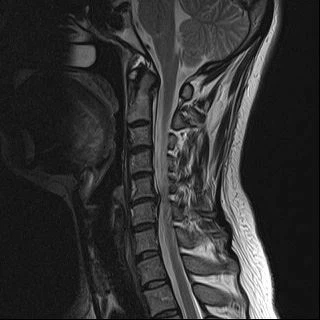

오늘 건강 정보는 목디스크 증상과 원인에 대해 알아보고 목디스크에 좋은 운동을 소개드리겠습니다. X-ray로 목을 촬영해보면 목뼈가 c 곡선을 유지하는 것이 정상이라고 합니다. 하지만 휴대전화와 태블릿을 사용함으로써 머리를 숙이고, 책상 앞에 앉아 책을 보는 시간이 많거나, 잘못된 자세를 취하고 있다면 목뼈의 배열이 흐트러지는 경우가 많습니다.

목을 받쳐주는 뼈를 경추라고 하는데 여기는 뼈가 7개 있고 이 뼈 마디마다 디스크라는 것이 있습니다. 이 디스크의 역할은 척추 뼈 사이에 충격을 완화하고 운동할 수 있게 합니다. 목디스크는 퇴행성 척추 질환으로 목 주위 근육, 인대가 장기간 압력을 받고 퇴행하여, 디스크가 자신의 역할을 하지 못하고 밀려나고 통증과 같은 목디스크 증상을 보이는 질병입니다.

이 디스크의 위치가 어디에 있는지에 따라 목 이외에도, 손이 저리거나 어깨가 아프고 두통과 같은 다른 목 디스크 증상을 일으킬 수 있습니다. 만약 여러분이 디스크를 그대로 방치하면, 몸이 마비되거나 호흡이 곤란한 상황에 처할 수 있기 때문에 목디스크 관리에 관심을 가져야 합니다.

척수라는 중추신경이 목뼈를 통과하고 목 아래 감각과 운동신경에 영향을 미치기 때문에 목디스크 증상이 나타날 경우 신속한 대책이 필요합니다. 목디스크 치료는 일반적으로 초기 단계에서 대부분의 환자가 물리치료 또는 약물을 통해 개선됩니다. 그렇지 않으면 신경 성형술과 차단술이라는 뼈 주사 목 디스크 치료법을 사용합니다. 이 치료법은 통증이 나타나는 신경 부위에 약물을 주입하는 것입니다. 치료로 질병을 완전히 치료하는 것이 아니라 염증을 완화하고 통증을 줄이는 것이 중요합니다.

3개월 이상 비수술적 치료를 받았음에도 불구하고, 증상이 호전되지 않는다면 목디스크 수술을 고려할 필요가 있습니다. 인조 디스크를 삽입하기 위해 절개를 통해 디스크를 제거하고 뼈를 하나로 묶는 것과 내시경 수술로 빠져나온 수핵 자체만 제거하는 방법이 있습니다.